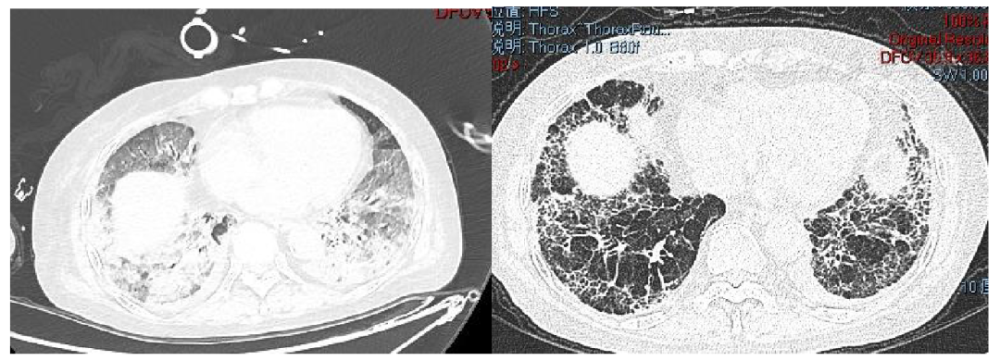

肺纖維化高發(fā)

《Nature Medicine》2021年發(fā)表了“Post-acute COVID-19 syndrome”,研究指出呼吸困難在60-100天的隨訪(fǎng)期內的發(fā)生率為42%-66%,有6.6%的患者因持續低氧血癥需要補充氧氣?;颊叱鲈汉?個(gè)月評估發(fā)現約25%的輕度至中度病例存在纖維化,在重癥病例居多的隊列中,約65%的康復者存在肺纖維化。